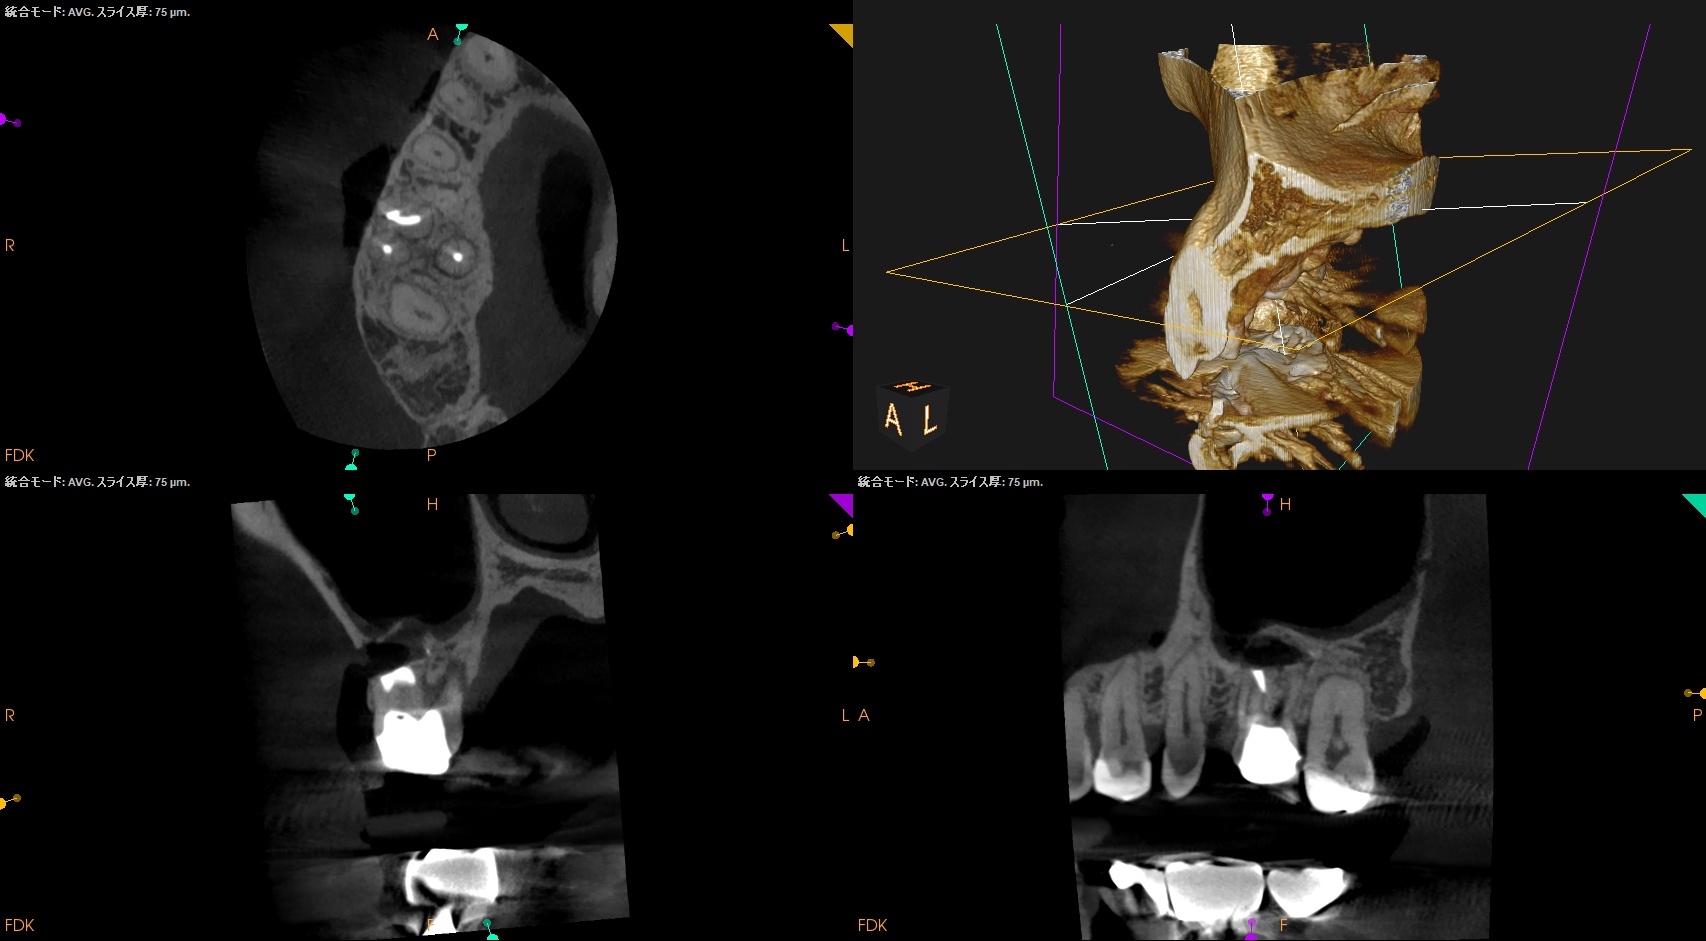

Pre-op Endo test(2025.8.25)

MB

DB

P

MB,DB,P全ての根管に根尖病変がある。

PのP側皮質骨はかなり減少している。

これが歯周病が原因か?と言えば、

術前の検査で歯周ポケットが正常値(Within Normal Limit)なため、恐らくエンドが原因でこのようになっているのだろう、と推測できる。

B

問題はないだろう。